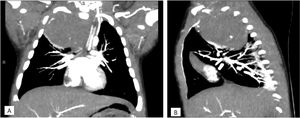

Radiografía de tórax. A)Proyección anteroposterior. Opacidad completa en el lóbulo superior derecho, con desplazamiento mediastínico hacia el lado contralateral, con buena aireación de los demás campos pulmonares, sin derrame pleural asociado. B)Proyección lateral. Opacidad en el segmento posterior del lóbulo superior del pulmón derecho, de morfología nodular.